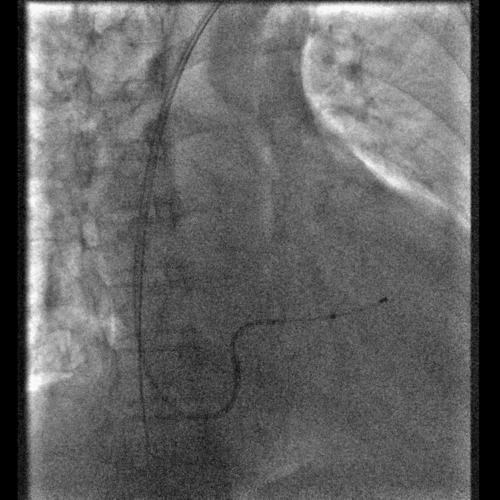

鞘中鞘的使用

果断选择鞘中鞘进入静脉分支,既能顺利通过扭曲,又能给电极提供更好的支撑力

美敦力的左室导线完美兼容鞘中鞘,提高植入成功率

右室右房电极的植入